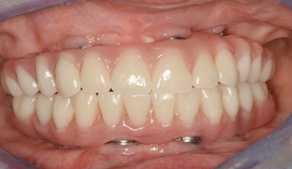

As an alternative to the relatively expensive traditional hybrid restoration that the senior population may perceive as unattainable at their age, an immediate-load all-resin provisional may often be a reasonable option as an entry-level prosthesis. This can serve for extended periods or indefinitely, and when made with a sufficient volume of resin and opposing a light occlusion such as a maxillary denture, it can offer the benefit of fixed retention at a significant reduction in expense (Figure 15 and Figure 16). Technology involving a guided approach for placing three implants universally in the same sites with pre-manufactured, one-size-fits-all bar components in the mandible can now allow placement of a final restoration in one day, again at a significantly reduced cost (Figure 17 and Figure 18).24-26 Both of these fixed options—the resin long-term provisional and the three-implant bridge—are economically comparable to the most commonly considered implant prosthesis for elderly patients, the two-implant overdenture. In contrast to the latter, however, both fixed restorations offer significant advantages in bite force, bone preservation, maintenance, and patient satisfaction that are simply unachievable with the removable implant overdenture prosthesis.27-31

Fig 17. A three-implant fixed bridge may be an immediate-load alternative for a fixed restoration as opposed to a two-implant overdenture. In addition to significant cost reduction due to pre-manufactured components, the final long-term restoration is delivered on the day of surgery.

Figure 17

Fig 18. A three-implant fixed bridge may be an immediate-load alternative for a fixed restoration as opposed to a two-implant overdenture. In addition to significant cost reduction due to pre-manufactured components, the final long-term restoration is delivered on the day of surgery.

Figure 18